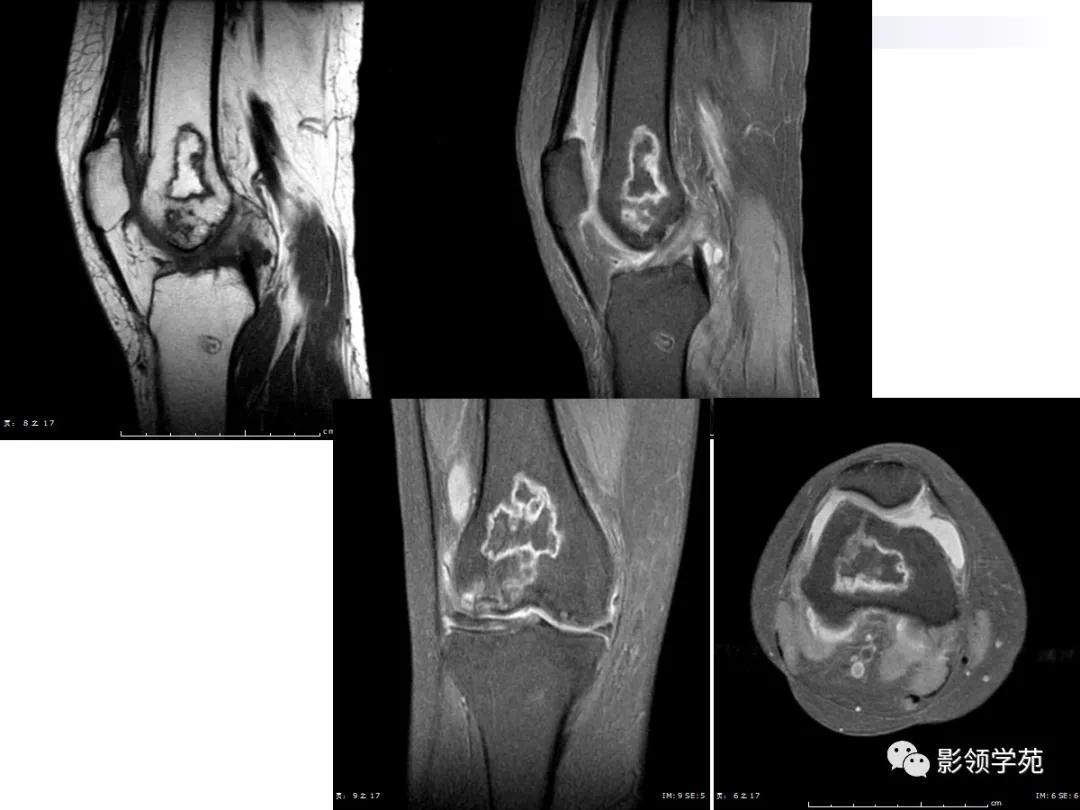

病例2:女性,45岁,病史:临床诊断SLE10年,膝关节疼痛4年。

MRI:呈不规则片状、斑片状混杂信号,病灶中央T1WI呈等、低信号,T2WI等、高信号,内部信号不均匀。

CT:呈不规则骨质吸收破坏伴环状或斑片状高密度钙化

MR:T1及T2均呈不规则的混杂片状低信号影,周围可见线状低信号单环征

患者因临床反复发作,新旧病灶同时存在,所以骨梗死以多发性、多形性、多期表现并存。